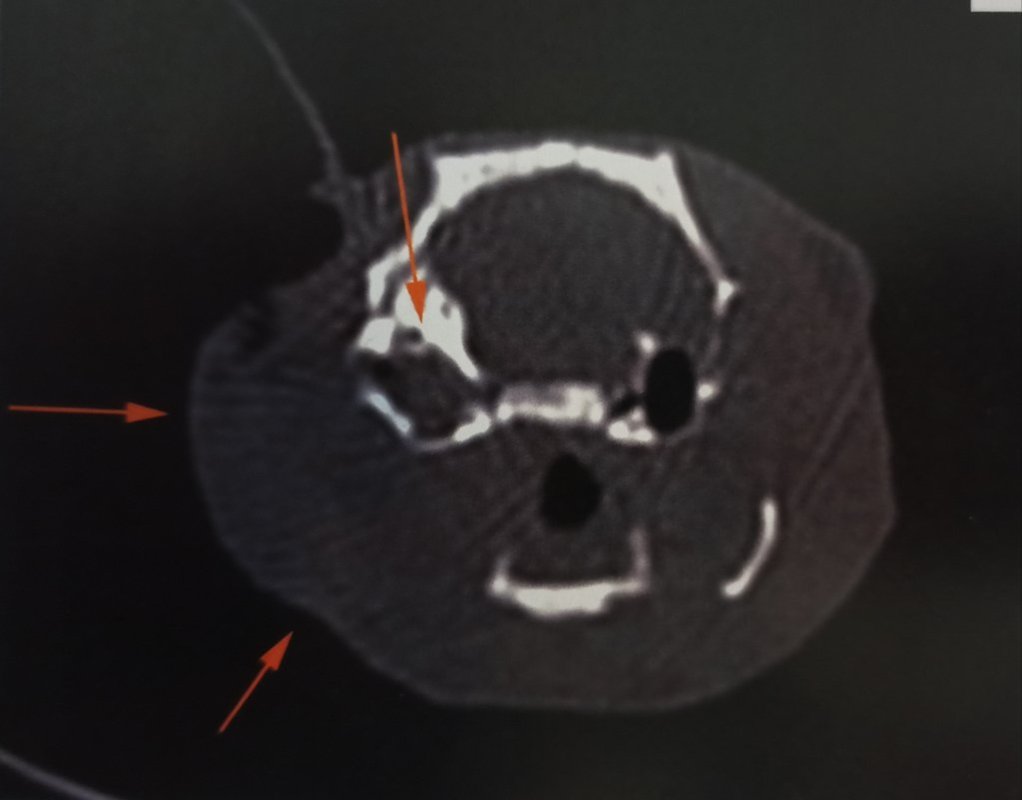

Et effectivement, pour le coup c'était ça. On ne le voit pas de l'extérieur mais il y a un gros gonflement autour de la bulle tympanique, c'est ça qui a décalé sa mâchoire en fait, et malheureusement cela a également atteint le cerveau...

Une chirurgie est possible pour la partie hors du cerveau, ce qui pourrait permettre de le rendre plus confortable pour manger, mais ce n'est pas sans risque d'empirer les choses, et quoi qu'on fasse on n'a pas d'espoir de guérison, seulement de lui faire gagner un peu de temps en gérant au mieux douleur et inconfort. Elle m'a fait une prescription de tramadol à ajouter au reste s'il semble avoir mal.

Je vous partage les images parce que vu le prix qu'elles m'ont coûtées autant que tout le monde en profite ><